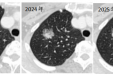

省医在茂名 名医零距离丨小结节差点变成“大问题”?专家提醒:定期复查很重要